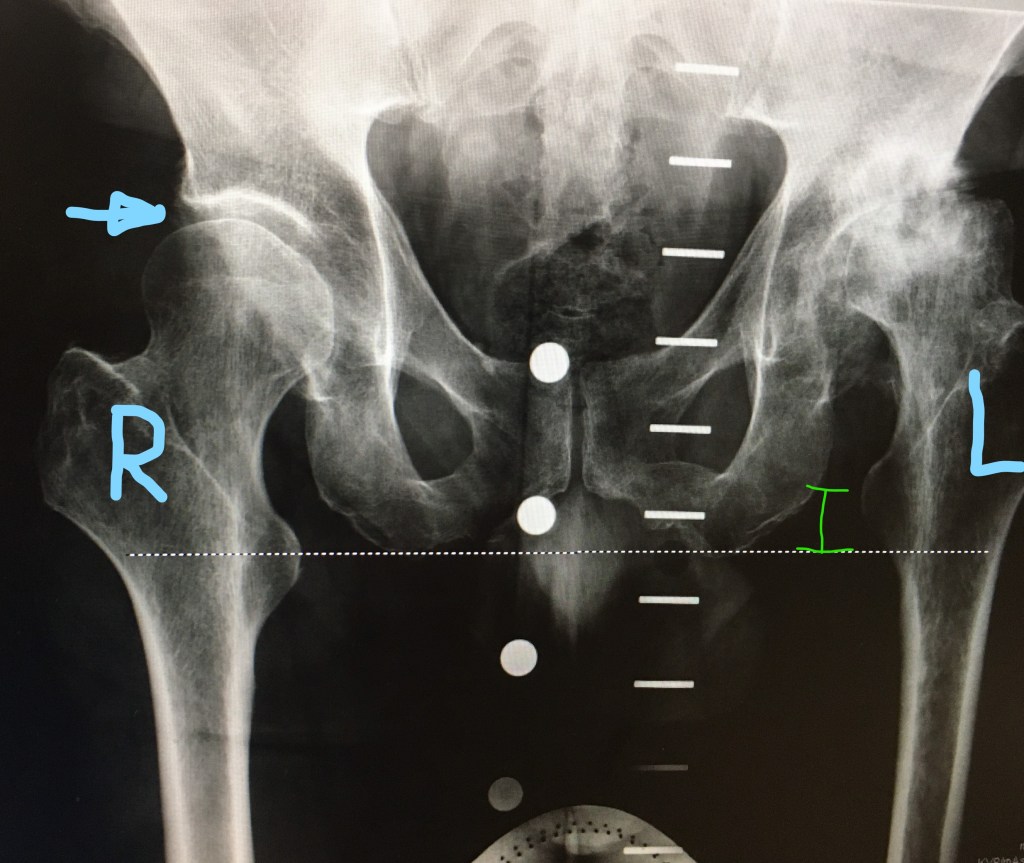

Pre surgery

In the pre surgery image the right hip shows a normal layer of cartilage (at the blue arrow). The x-ray image shows this as a gap between the bones. This is completely absent in the left hip. There the cartilage has been abraded away by the arthritic femoral head. As a result the left leg bone had pushed its way up into the hip socket and was bearing bone on bone. As a result, my left leg had become shorter over time, by more than one centimeter. Post surgery, the artificial hip holds the left leg bone in its correct position. As a result, my two legs are once again the same length. The horizontal dashed white line shows that the two leg bones are aligned post surgery. A displacement of one centimeter is seen in the presurgery case (green spacer)